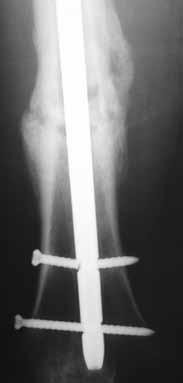

Figures 18a through 18c show injuries sustained by a 22-year-old woman after falling 45 feet while mountain climbing. After being airlifted to the nearest trauma center, her arterial blood gas was 7.21, pO2 84, pCO2 48, and base arterial blood gas was 7.21, pO2 84, pCO2 48, and delta base -11 mmol/L. Her Hg is

8.7 and her resuscitation is ongoing. Based on this data, what would be the best management of her orthopaedic injuries?